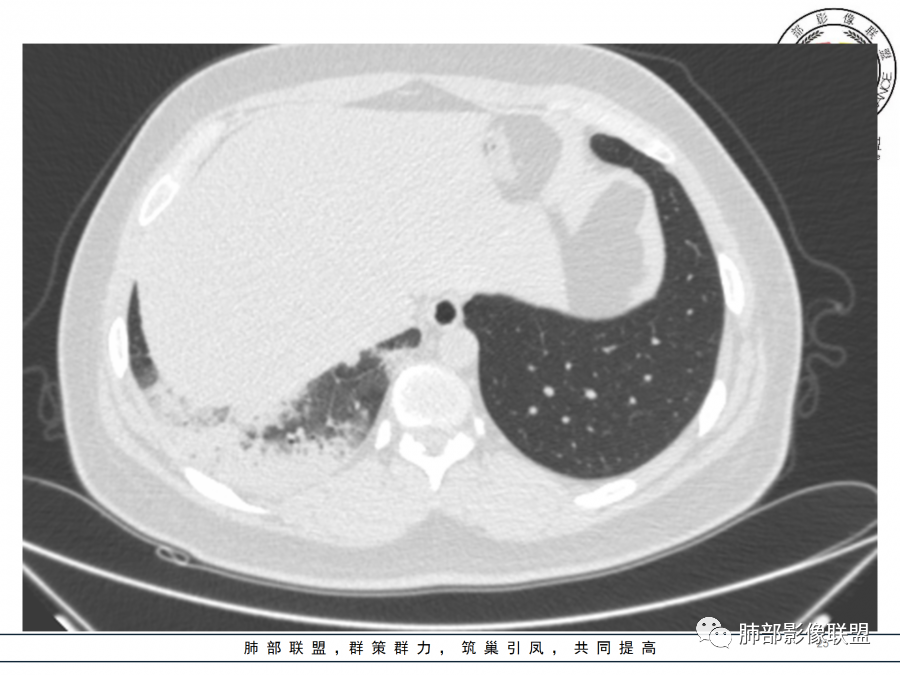

年轻女性,急性病史,发热,WBC17.42*10^9/L,NE%82.8%,

痰革兰染色示:G-杆菌1+、G+球菌1+,未检出真菌,抗酸染色阴性。

大片实变影

细菌性感染?隐球菌?结核?梗死?

淋巴瘤?肺炎型肺癌?支原体?病毒?

1.年轻女性,咳嗽、发热(38.8°),起病急,血象高。影像上大片实变影为主,一般会首先考虑细菌性肺炎,尤其是肺炎链球菌感染等。疗效不满意时考虑其他。

2.影像上怀疑其他病灶的理由有:

1)实变影为大小不等多中心性。

2)沿胸膜下分布趋势(不同于大叶性肺炎的肺叶“造型”)。

3)周围较大范围磨玻璃影及小叶间隔增厚。

4)病灶体积增大明显(叶间裂推移)。

3.腺病毒肺炎可以符合上述改变:实性密度,间质分布为主等。

4.隐球菌感染可以符合上述改变:胸膜下多中心实变密度为主,磨玻璃晕等。但隐球菌临床症状大多隐匿、迁延,影像变化缓慢。

5.本例患者血象高,影像渗出明显,尚不能排除混合感染可能。